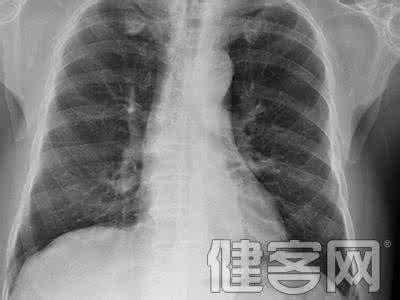

肺癌是一种很严重的病,肺癌不仅影响了生活,而且给患者带来了生理上的疼痛和心理的上折磨,给人带来对死亡的恐惧,如果治愈后肺癌再复发该如何是好呢,下面就来看看这方面的内容吧。

肺癌复发是指原发性肺癌经过手术等治疗,癌肿消退后,经过一段时期,在原来的部位重新长出性质相同的癌肿。从临床总结中发现,肺癌复发后的治疗难于复发前的治疗。肺癌复发的原因有很多,但是无论哪种情况引起的,都要根据复发的原因采取有效的治疗方法。